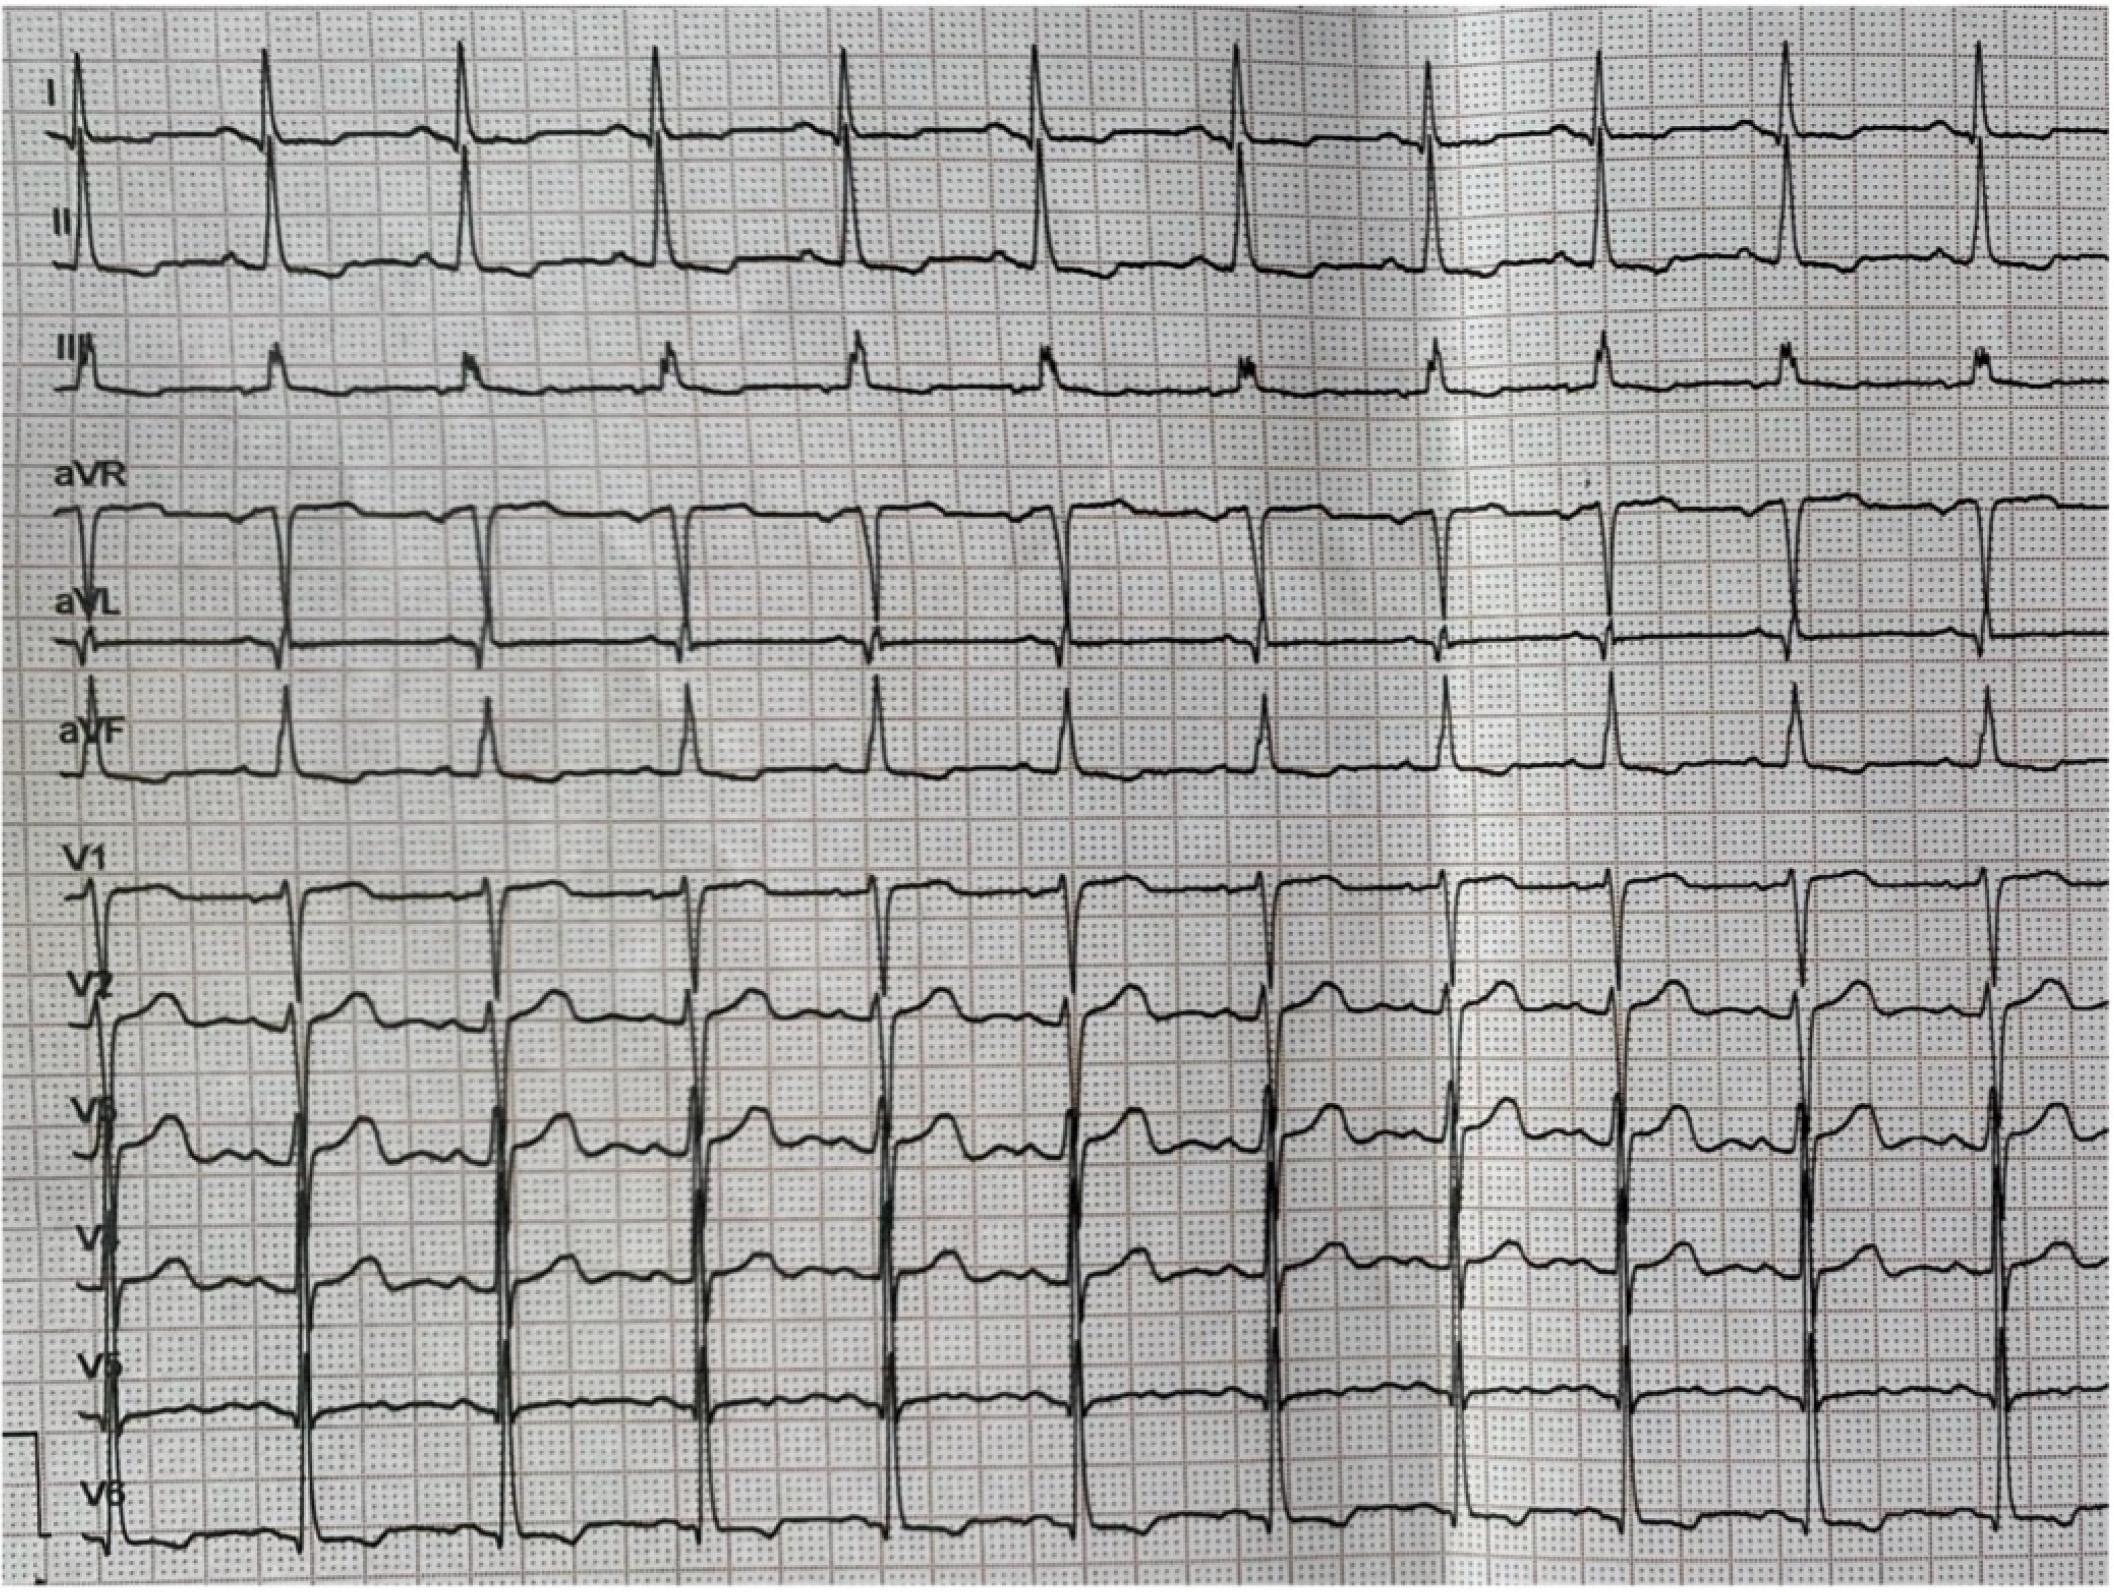

Figure 1.

Figure 2

Figure 3

Figure 4

Figure 5

Figure 6

Figure 7

Figure 8